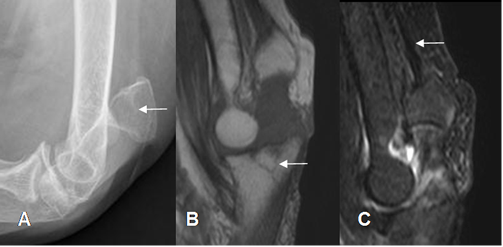

Fig 42. Lesión del tríceps, por avulsión del olécranon.

A: Rx lateral. Avulsión del olécranon, con desplazamiento superior.

B: RM sagital T1. Adicional a la avulsión , existen fracturas en el cubito distal.

C: RM sagital STIR. Cambios inflamatorios, con tendón del tríceps normal.